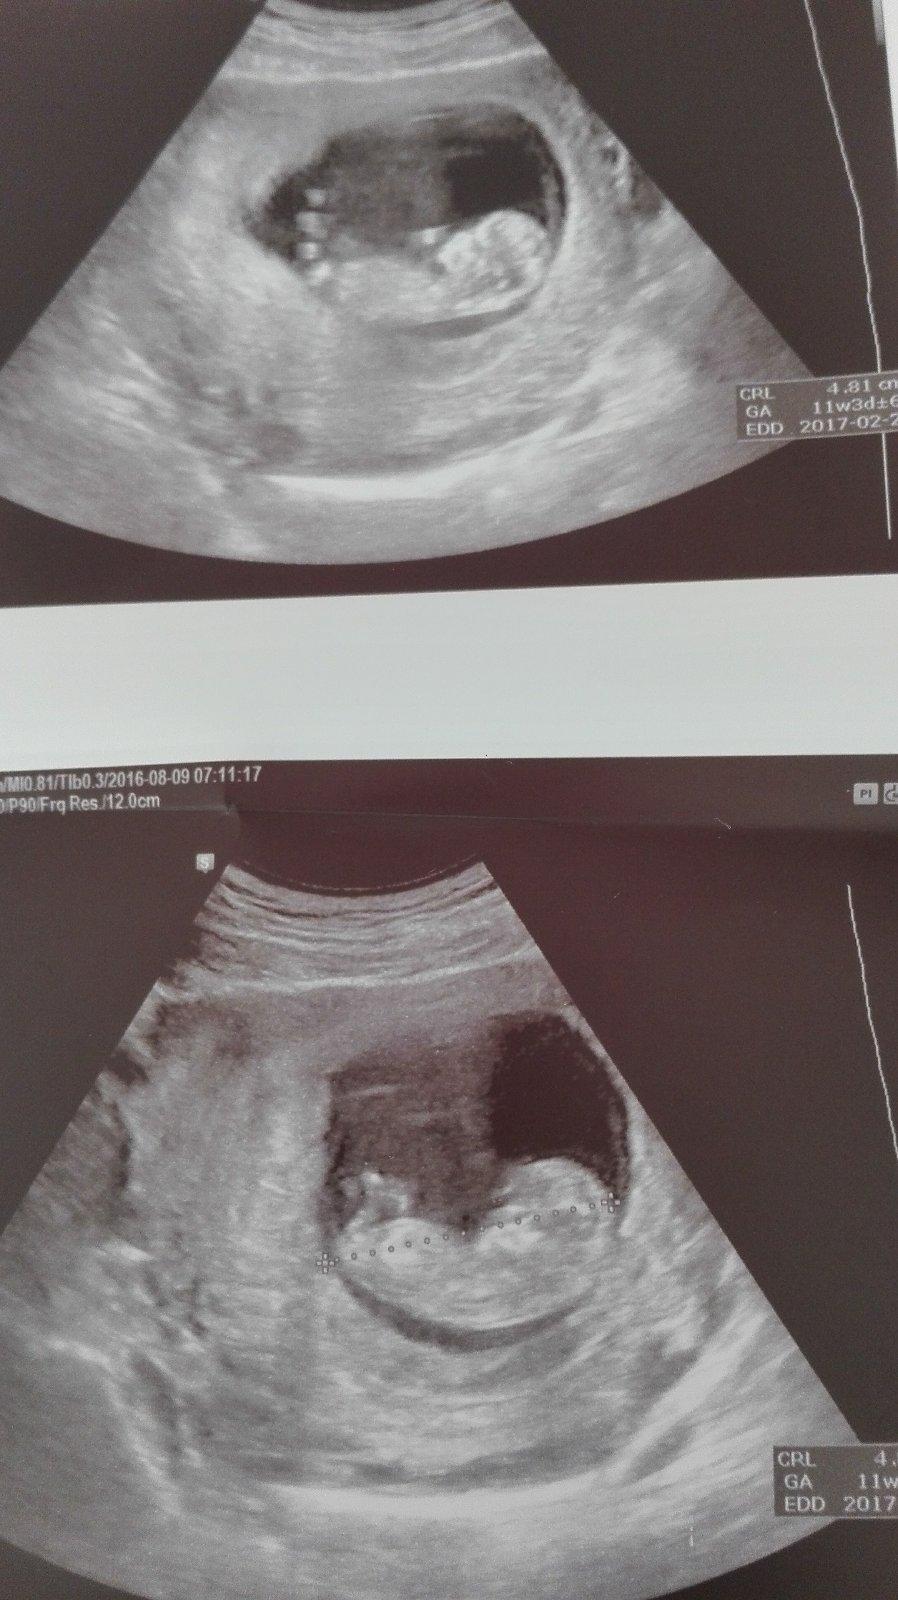

Ahojte baby tak my sme na prelome 2/2017 3/2017 ale zatiaľ máme TP 25.2.2017 dr.ani nevravel kedy :/

@hateria v 11- 13tt by si mala ísť na prvý skrining.moj doky pozerá cez bruško,vaginalny uzv nemá a na skríning idem 23.8. tak uvidíme...ale s prvým synom mi v prvom trimestri robili vaginálne a s druhým cez brucho... 🙂

@hateria aby som bola presná,v teho knižke sa píše prenatalna diagnostika v I. trimestri od 11+1tt do 12+6tt

@hateria inak v rámci tohto skríningu sa práve zisťuje prítomnosť nosovej kostičky a sijove prejasnenie plus ďaľšie veci....veľkosť,srdiecko,pohyby atd.

Ja budem 12+0 keď pôjdem na ten uzv.

@hateria krv by mala byt medzi 9 a 14 tyzdnom a sono na Down medzi 11+3 a pred 14 tyzdnom